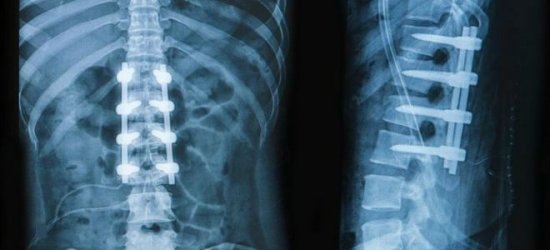

Диагностика

Почему болит низ спины, может установить только врач. Ни в коем случае не следует заниматься самодиагностикой и самолечением. Диагноз ставится на основании жалоб больного, клинических проявлений, анамнестических данных, результатов инструментальных методов исследования. Пациенту назначают рентгенографию, миелографию, МРТ, КТ и другие виды обследований.

Компьютерная томография является эффективным и высокоинформативным способом выявления различных структурных изменений в позвоночнике, вызванных травматизацией, инфекционным процессом, опухолевыми образованиями, остеопорозом и другими заболеваниями. В основе миелографии лежит применение контрастирующего вещества. Метод применяют при подозрении на стеноз позвоночного канала, грыжевых образованиях, опухолях и других патологических процессах в позвоночнике.

Неотъемлемая составляющая диагностики болей в спине – инструментальные исследования